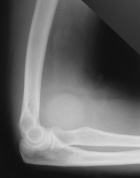

62 y/o female presents with a few months of an increasing left elbow mass, discomfort with activity, relieved by rest

PMH/PSH: Breast cancer treated with lumpectomy, nonsmoker

PE: Large nontender mass anterior L elbow, only a few degrees loss of ROM at elbow, no LAN, neurovasculary intact